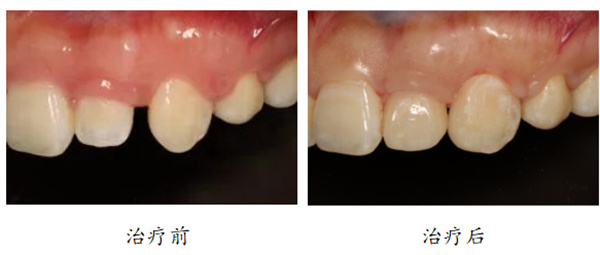

3、牙齿形态异常

“我有一个牙齿好小哦,和别的牙长得就不一样。”

“有一些朋友的个别牙齿长得比较小,看起来不太协调,或者是形状比较奇怪,这时候就可以用个贴面在牙齿外面包装一下,让他们看起来和其它的牙齿一样漂亮。”